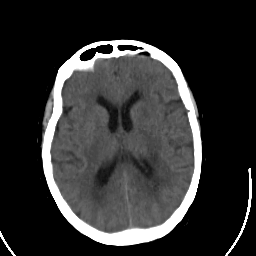

Stroke CT #2 -- Slice #14

[Home][Help][Clinical] Slice 14